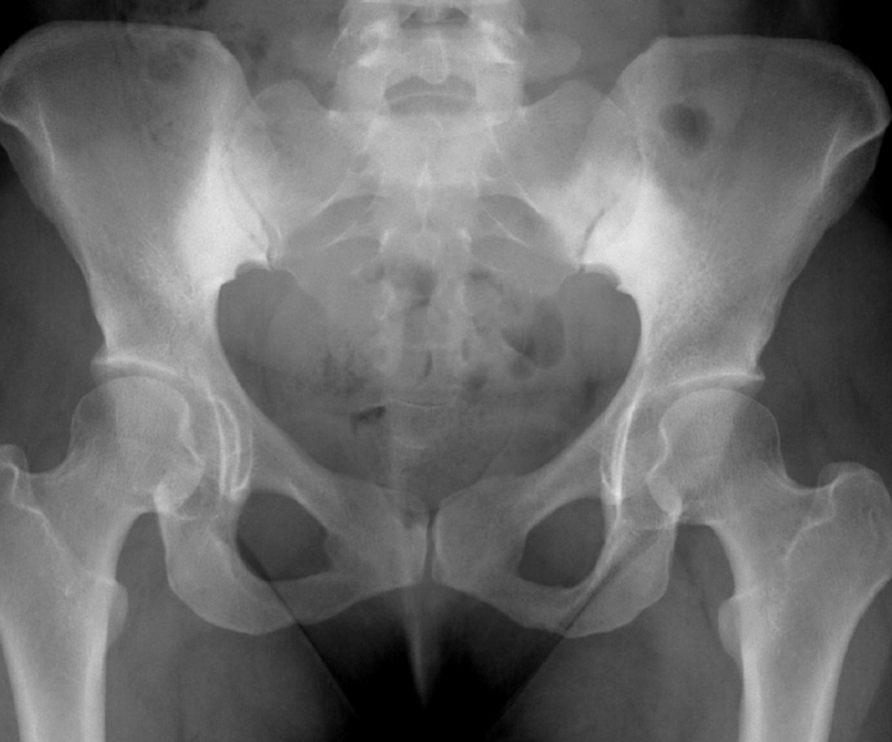

Crohn's disease patient complains of bilateral hip pain.

What is avascular necrosis?